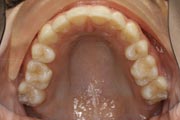

Crowding

After